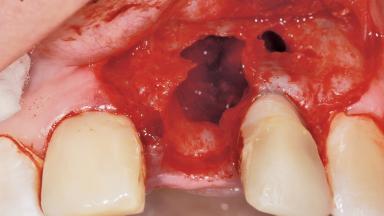

Late Placement of an Implant in a Maxillary Left Central Incisor Site

A 36-year-old female patient was referred for the replacement of the upper left central incisor (tooth 21), which had fractured. Although the tooth had been asymptomatic for many years, the crown began to loosen, at which time she presented to her dentist for an assessment. Teeth 21 and 22 had both been endodontically treated many years previously. She was a healthy individual and a non-smoker.

The crown of tooth 21 was splinted to the adjacent teeth with composite resin, and the gingiva was inflamed.